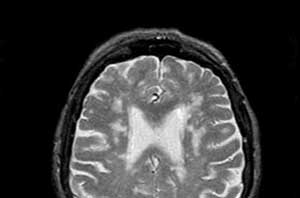

В дополнение к консультации невролога и выполнению клинических анализов крови, для диагностики заболеваний специалисты применяют:

- магнитно-резонансную томографию, особенно для выявления диффузно очаговой перивентрикулярной лейкоэнцефалопатии;

Современные технологии визуализации, такие как магнитно-резонансная томография (МРТ), также играют важную роль в диагностике и мониторинге прогрессирования заболевания. МРТ позволяет детально оценить состояние белого вещества мозга и выявить изменения, характерные для различных форм лейкоэнцефалопатии. Это, в свою очередь, помогает врачам более точно подбирать терапию и оценивать ее эффективность.